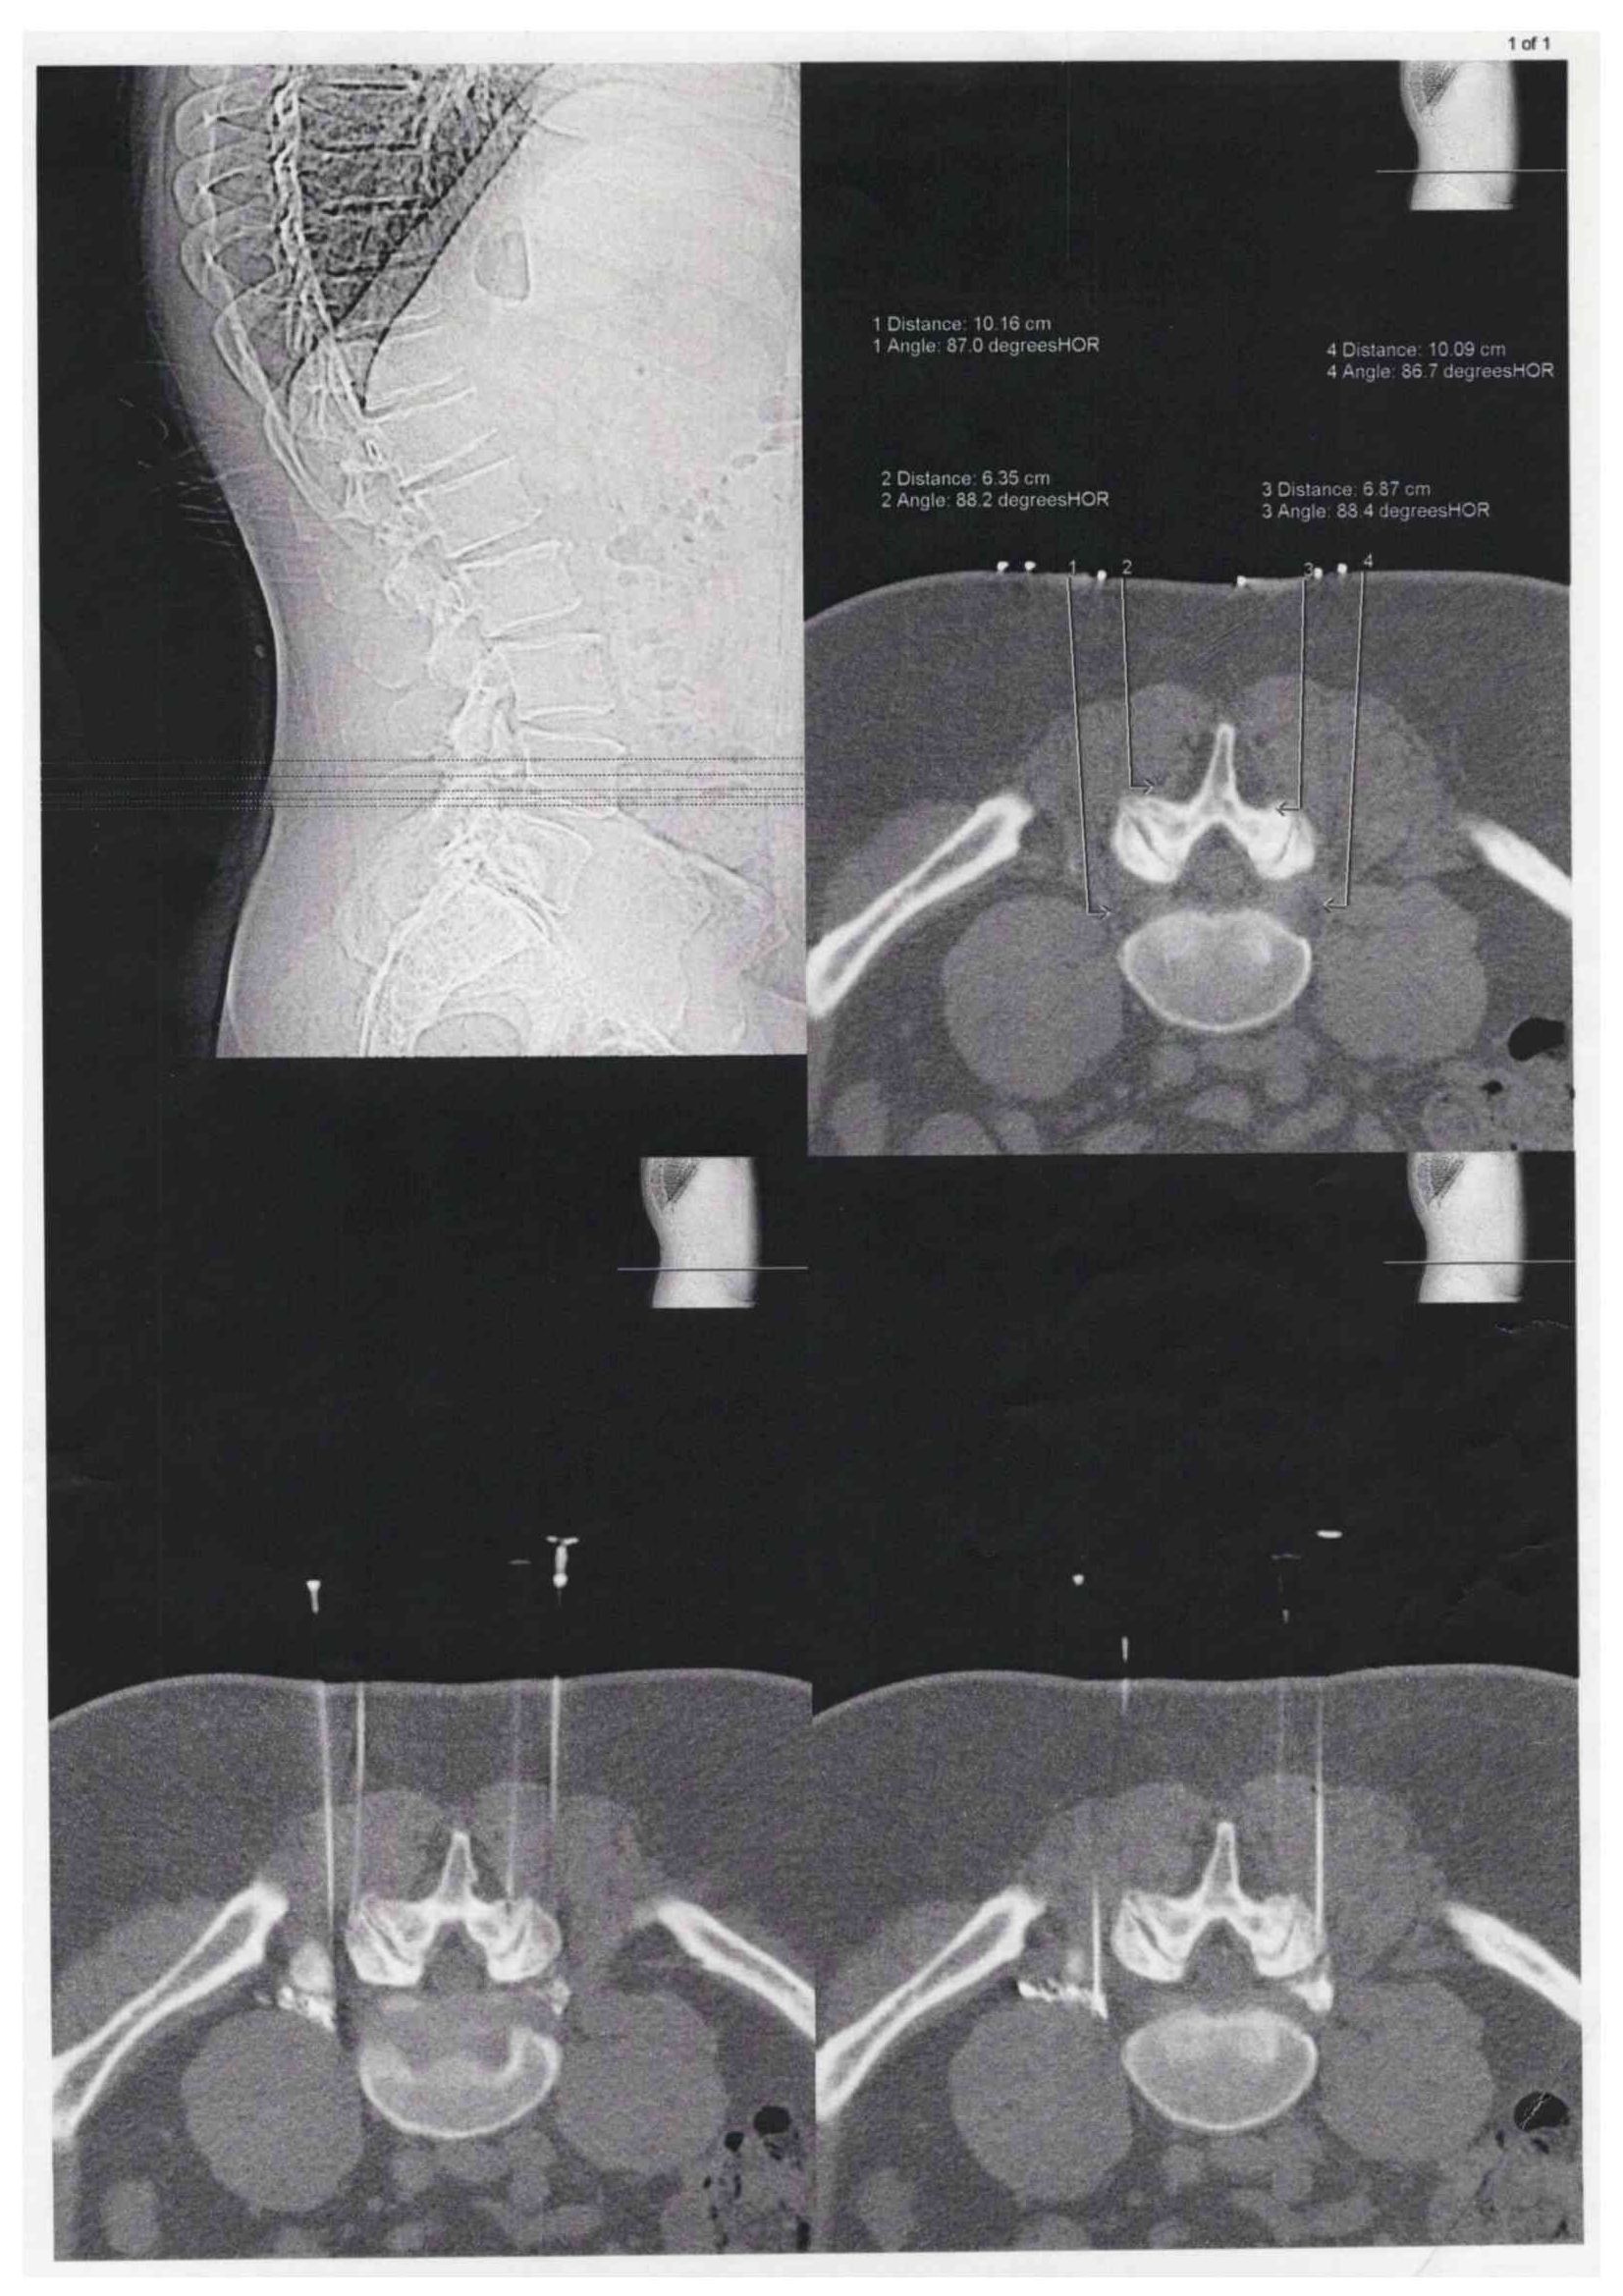

Bei der CT-gesteuerten Schmerztherapie handelt es sich um ein besonders präzises Verfahren. So werden per computertomographischer Planung in Bauchlage des Patienten feine Nadeln millimetergenau an die schmerzenden Strukturen wie Wirbelgelenke oder Nervenwurzeln sowie ggf. auch an einen Bandscheibenvorfall herangeführt. Nach Kontrolle der Nadellage werden z.B. die Wirbelgelenke infiltriert oder aber ein Nervenwurzel mit betäubenden und entzündungshemmenden Medikamenten umspritzt.

Prozedur : Wie wird die CT- gesteuerte Schmerztherapie durchgeführt?

Die Behandlung wird grundsätzlich in örtlicher Betäubung mit sehr feinen Nadeln vorgenommen. Der Patient liegt auf dem Bauch auf dem CT-Tisch. Zur genauen Höhenlokalisation der Schmerzstelle wird auf den Rücken ein Metallstreifen /Büroklammer geklebt. Ein so genanntes Topogramm, also eine Übersichtsaufnahme des entsprechenden Wirbelsäulenabschnittes wird angefertigt. Jetzt kann auf dem computertomographischen Schnittbild die Schmerzstelle lokalisiert werden. Auf dem Bearbeitungsmonitor können dann der exakte Eintrittspunkt der Nadel, der Winkel und die Tiefe, sowie die Stelle. in der gespritzt werden soll, ermittelt werden. All diese Parameter werden anschließend mit einem Laserpunkt auf dem Patienten dargestellt. Gefolgt von einer örtlichen Punktion nach steriler Säuberung der Haut kann die feine Punktionsnadel, die eine millimetergenaue Skalierung aufweist, am Schmerzpunkt platziert werden. Es folgt die CT- Kontrollaufnahme zur Dokumentation der exakten Nadellage. Um das Verteilungsmuster des zur verabreichenden Medikamente feststellen zu können, wird eine kleine Menge von verdünntem Kontrastmittel gespritzt. Dann werden Medikamente um die Nervenwurzeln verabreicht (PRT= Periradikuläre Schmerztherapie).